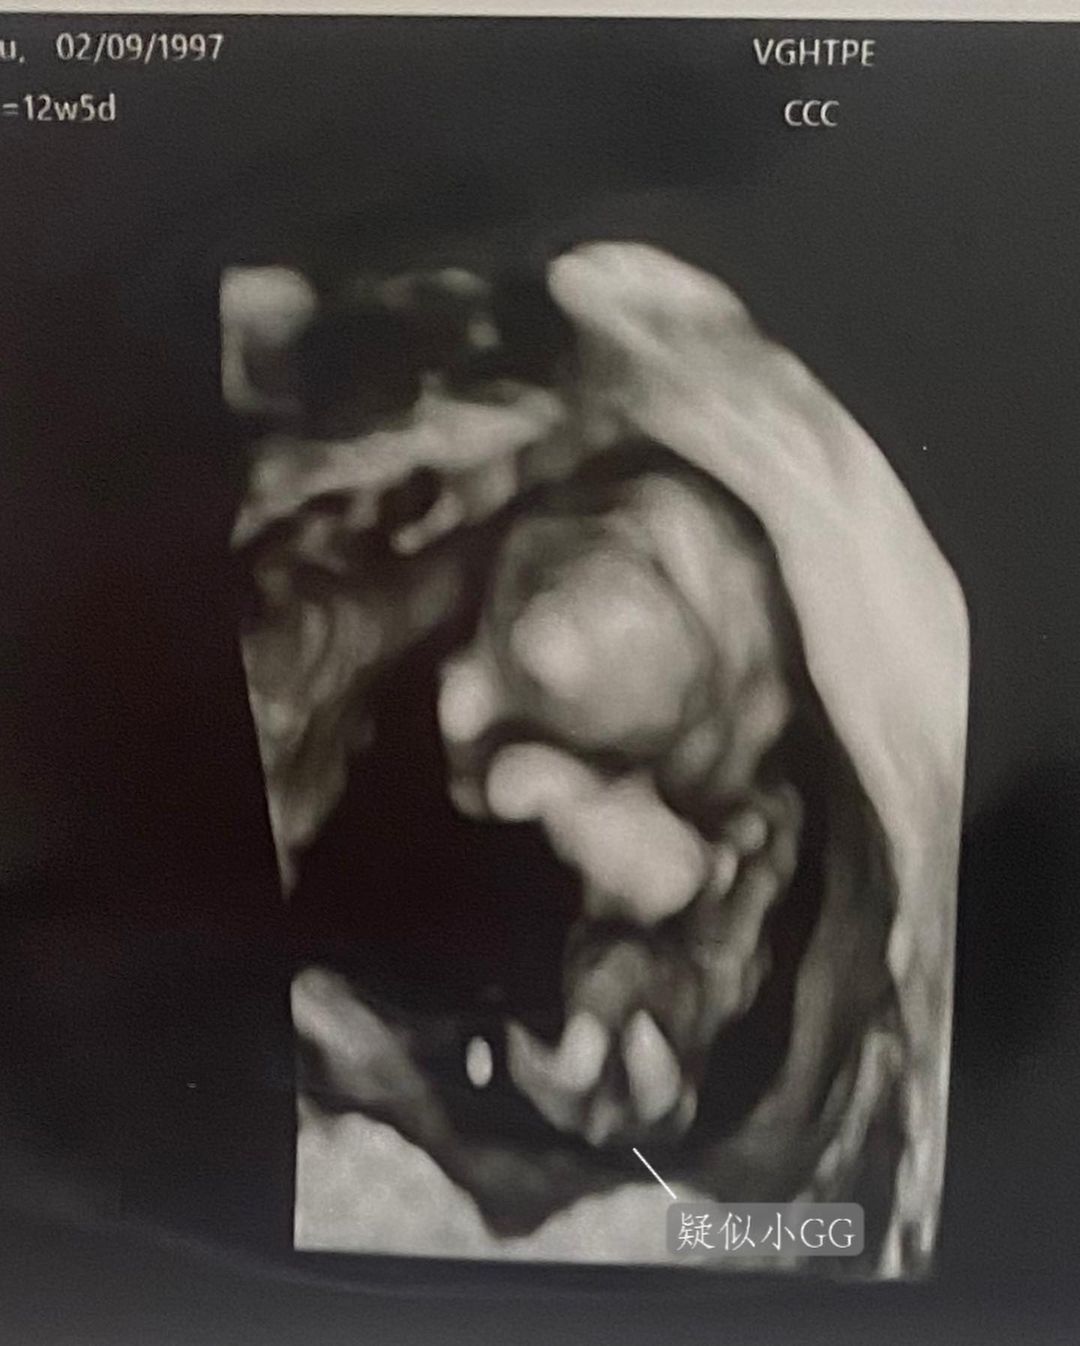

▼先前余祥銓和柔柔猜測此胎是男寶寶,沒想到猜錯了,是個女兒。柔柔26日發文說,先前照超音波時,疑似看到小GG的東西,所以才以為是男孩,余祥銓還搞笑說「真的『天賦異稟』,這麼小就看得到」。第二次產檢時,柔柔堅定不移說「是底迪,看到GG了」,沒想到護士默默說了一句「她明明就是女生……」,讓她哭笑不得。柔柔表示,對她來說是男是女都好,只要健康長大才是最重要的。